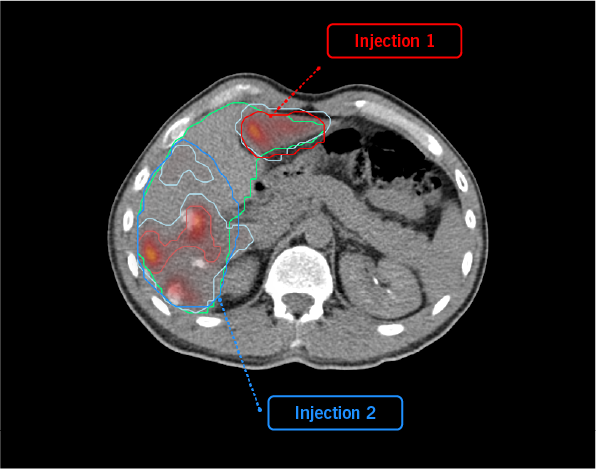

Multiple injections

Plan multiple activity injections for optimal dosage